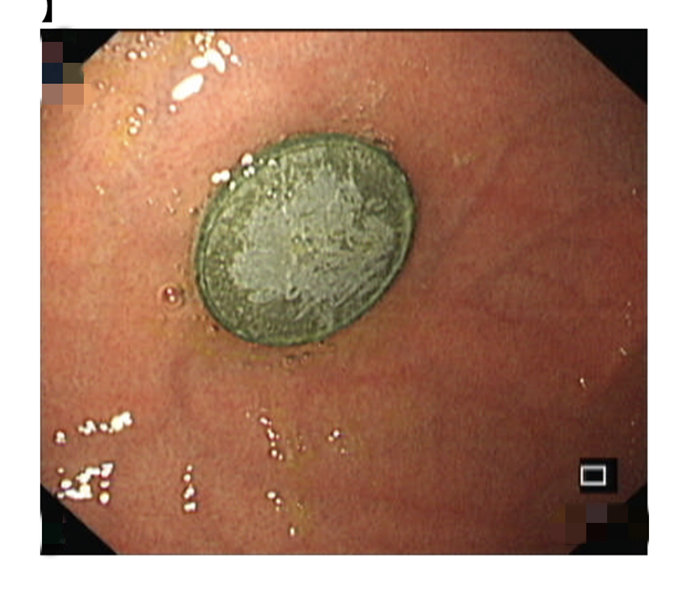

溫附二兒科消化專家胡偉國主任醫(yī)師會診后,立即為小京京開具X光片檢查,發(fā)現(xiàn)異物滯留于胃部,考慮到硬幣長時(shí)間在胃內(nèi)可能引起胃黏膜損傷,胡偉國馬上聯(lián)系麻醉科、內(nèi)鏡中心,在靜脈麻醉下為小京京行內(nèi)鏡下胃內(nèi)異物取出術(shù)。

術(shù)中發(fā)現(xiàn)硬幣果然還在胃里,好在胃黏膜無受損,胡偉國主任通過專用異物鉗很快將硬幣取出。該硬幣直徑約19毫米,已被胃液略微腐蝕。